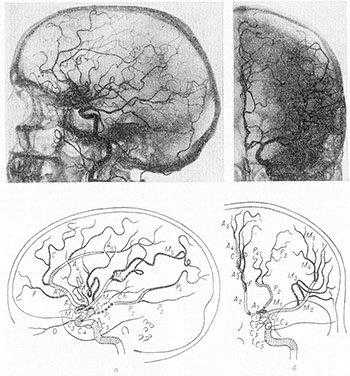

3D-модель церебральных артерий и вен

На фоне ядерного резонанса возникает слабый электромагнитный сигнал, который считывают при помощи чувствительных детекторов. Информацию обрабатывают, данные преобразуют в серию послойных снимков и транслируют на монитор компьютера.

МРТ сосудов головного мозга включает сканирование вен и артерий, изучение характера церебрального кровоснабжения. Объект исследования обладает выраженными парамагнетическими свойствами. Благодаря высокому содержанию воды жидкие среды обеспечивают гиперинтенсивный сигнал на фоне окружающих тканей. При необходимости МРТ артерий головного мозга можно проводить без использования контраста.